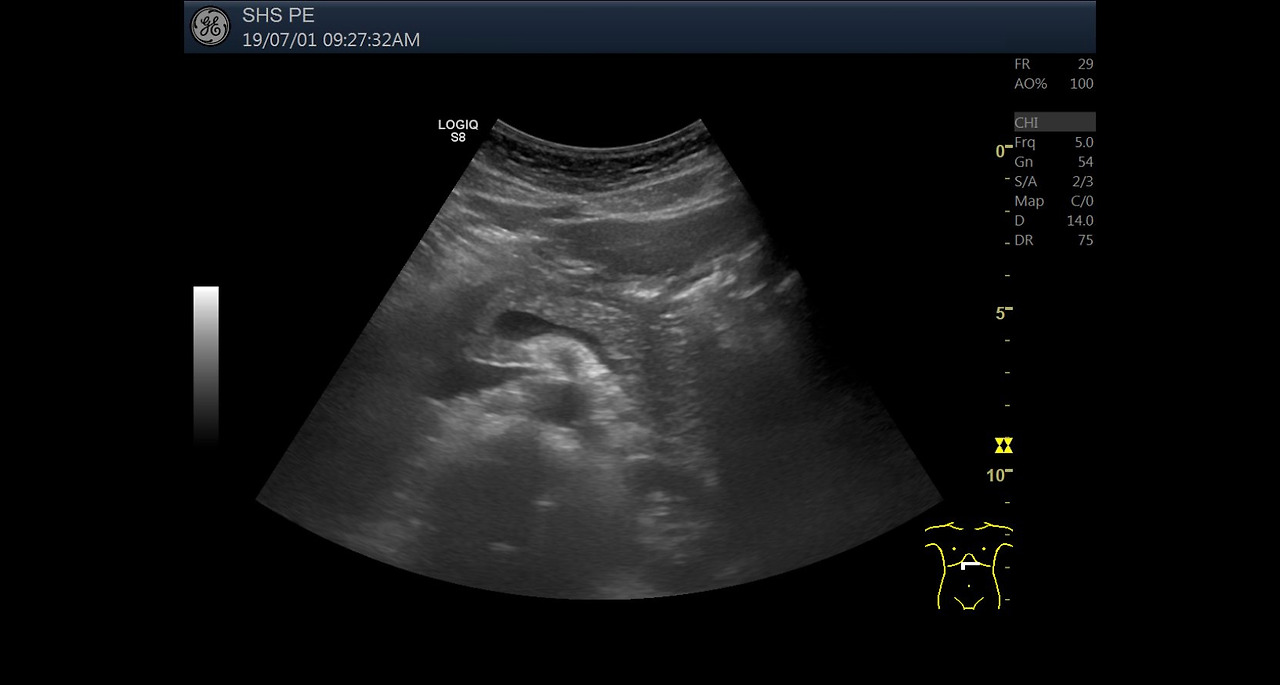

복부 초음파 검사는 내부 장기 상태를 실시간으로 확인할 수 있는 비침습적이고 안전한 검사 방법입니다. 많은 사람들이 건강검진이나 특정 증상이 있을 때 이 검사를 받는데, 이를 통해 다양한 질환이나 건강 상태를 확인할 수 있습니다. 특히, 복부 초음파는 간, 신장, 췌장, 담낭 등을 포함한 여러 장기의 상태를 검사할 수 있는 중요한 도구로 활용됩니다.

복부 초음파 검사는 환자에게 특별한 준비가 필요하지 않은 간단한 검사입니다. 보통 20분에서 30분 정도 소요되며, 검사 전에는 식사를 금지하거나 적당한 시간 동안 공복 상태를 유지해야 하는 경우가 많습니다. 초음파 검사에서는 젤을 피부에 바르고, 초음파 기기를 복부에 대고 화면을 통해 내부 장기를 확인합니다. 환자는 검사 동안 편안한 자세를 유지해야 하며, 검사 후에는 특별한 후유증이나 회복 시간이 필요하지 않습니다.